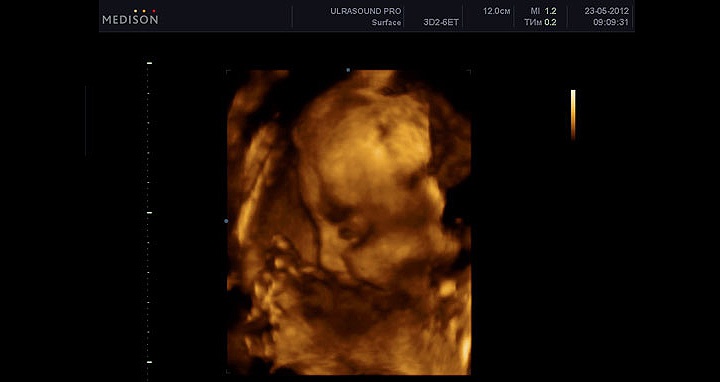

УЗИ на 31 неделе беременности

На 31 неделе может быть очередное УЗИ, которое часто является последним. Специалист проведет необходимые измерения, исключит пороки развития, измерит частоту сердечных сокращений и количество околоплодных вод. На этом сроке можно обнаружить пороки развития желудочно-кишечного тракта и мочеполовой системы. Обязательно оценят состояние плаценты и кровотока.

УЗИ позволяет оценить двигательную активность, дыхательные движения и сердцебиение малыша, а также исключить обвитие плода пуповиной.

При УЗИ на 31 неделе важно исключить отставание в развитии плода, что проверяется фетометрией.

Фетометрия (размеры плода) при УЗИ на 31 неделе беременности в норме

- БПР (бипариетальный размер) 73–87 мм.

- ЛЗ (лобно-затылочный размер) 93–109 мм.

- ОГ (окружность головки плода) 273–315 мм.

- ОЖ (окружность живота плода) 247–301 мм.

Нормальные размеры длинных костей при УЗИ на 31 неделе беременности

- Бедренная кость 54–64 мм.

- Плечевая кость 50–60 мм.

- Кости предплечья 44–52 мм.

- Кости голени 51–59 мм.

Во время процедуры делают допплерографию сосудов для оценки маточно-плацентарного и фетоплацентарного кровообращения.

При УЗИ также оценивают количество и качество околоплодных вод. Уменьшенное количество может быть связано с пороками мочевыводящей системы. Увеличенное количество может указывать на нарушения утилизации вод.